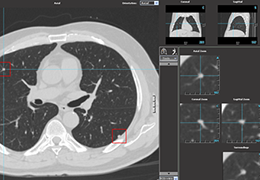

ANYTHINK 经导管主动脉瓣膜置换术分析系统